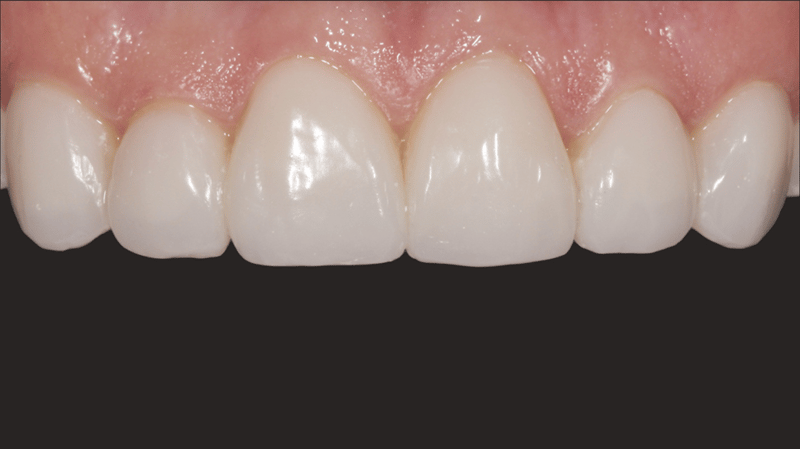

- Cementation Results: The final cementation resulted in a stable and esthetically pleasing veneer placement.

The procedure successfully addressed the patient’s esthetic concerns by masking the discoloration of her upper anterior teeth and achieving a natural, balanced look with her lower anteriors. The use of no-prep direct-bonded composite veneers provided a conservative, highly effective solution that respected both the patient’s financial constraints and desire for minimal invasiveness.